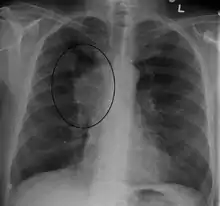

The main techniques of diagnosing SVCS are with chest X-rays (CXR), CT scans, transbronchial needle aspiration at bronchoscopy and mediastinoscopy.[6] CXRs often provide the ability to show mediastinal widening and may show the presenting primary cause of SVCS.[6] However, 16% of people with SVC syndrome have a normal chest X-ray. CT scans should be contrast enhanced and be taken on the neck, chest, lower abdomen, and pelvis.[6] They may also show the underlying cause and the extent to which the disease has progressed.[6]